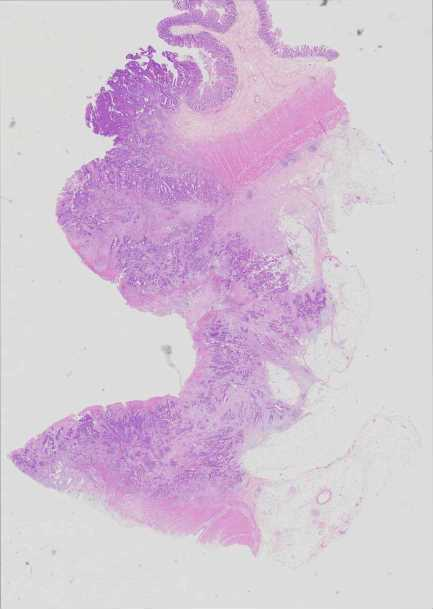

Use Case 4

240366843437

Overview Statistics B details